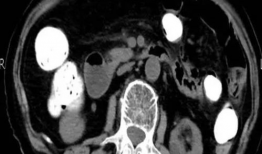

入腹视频,揭秘人体内部神秘世界

亲爱的读者,你是否曾在某个闲暇时刻,被那些深入人心的视频所吸引?那些视频,仿佛能直接钻进你的心里,让你在屏幕前驻足良久。今天,就...